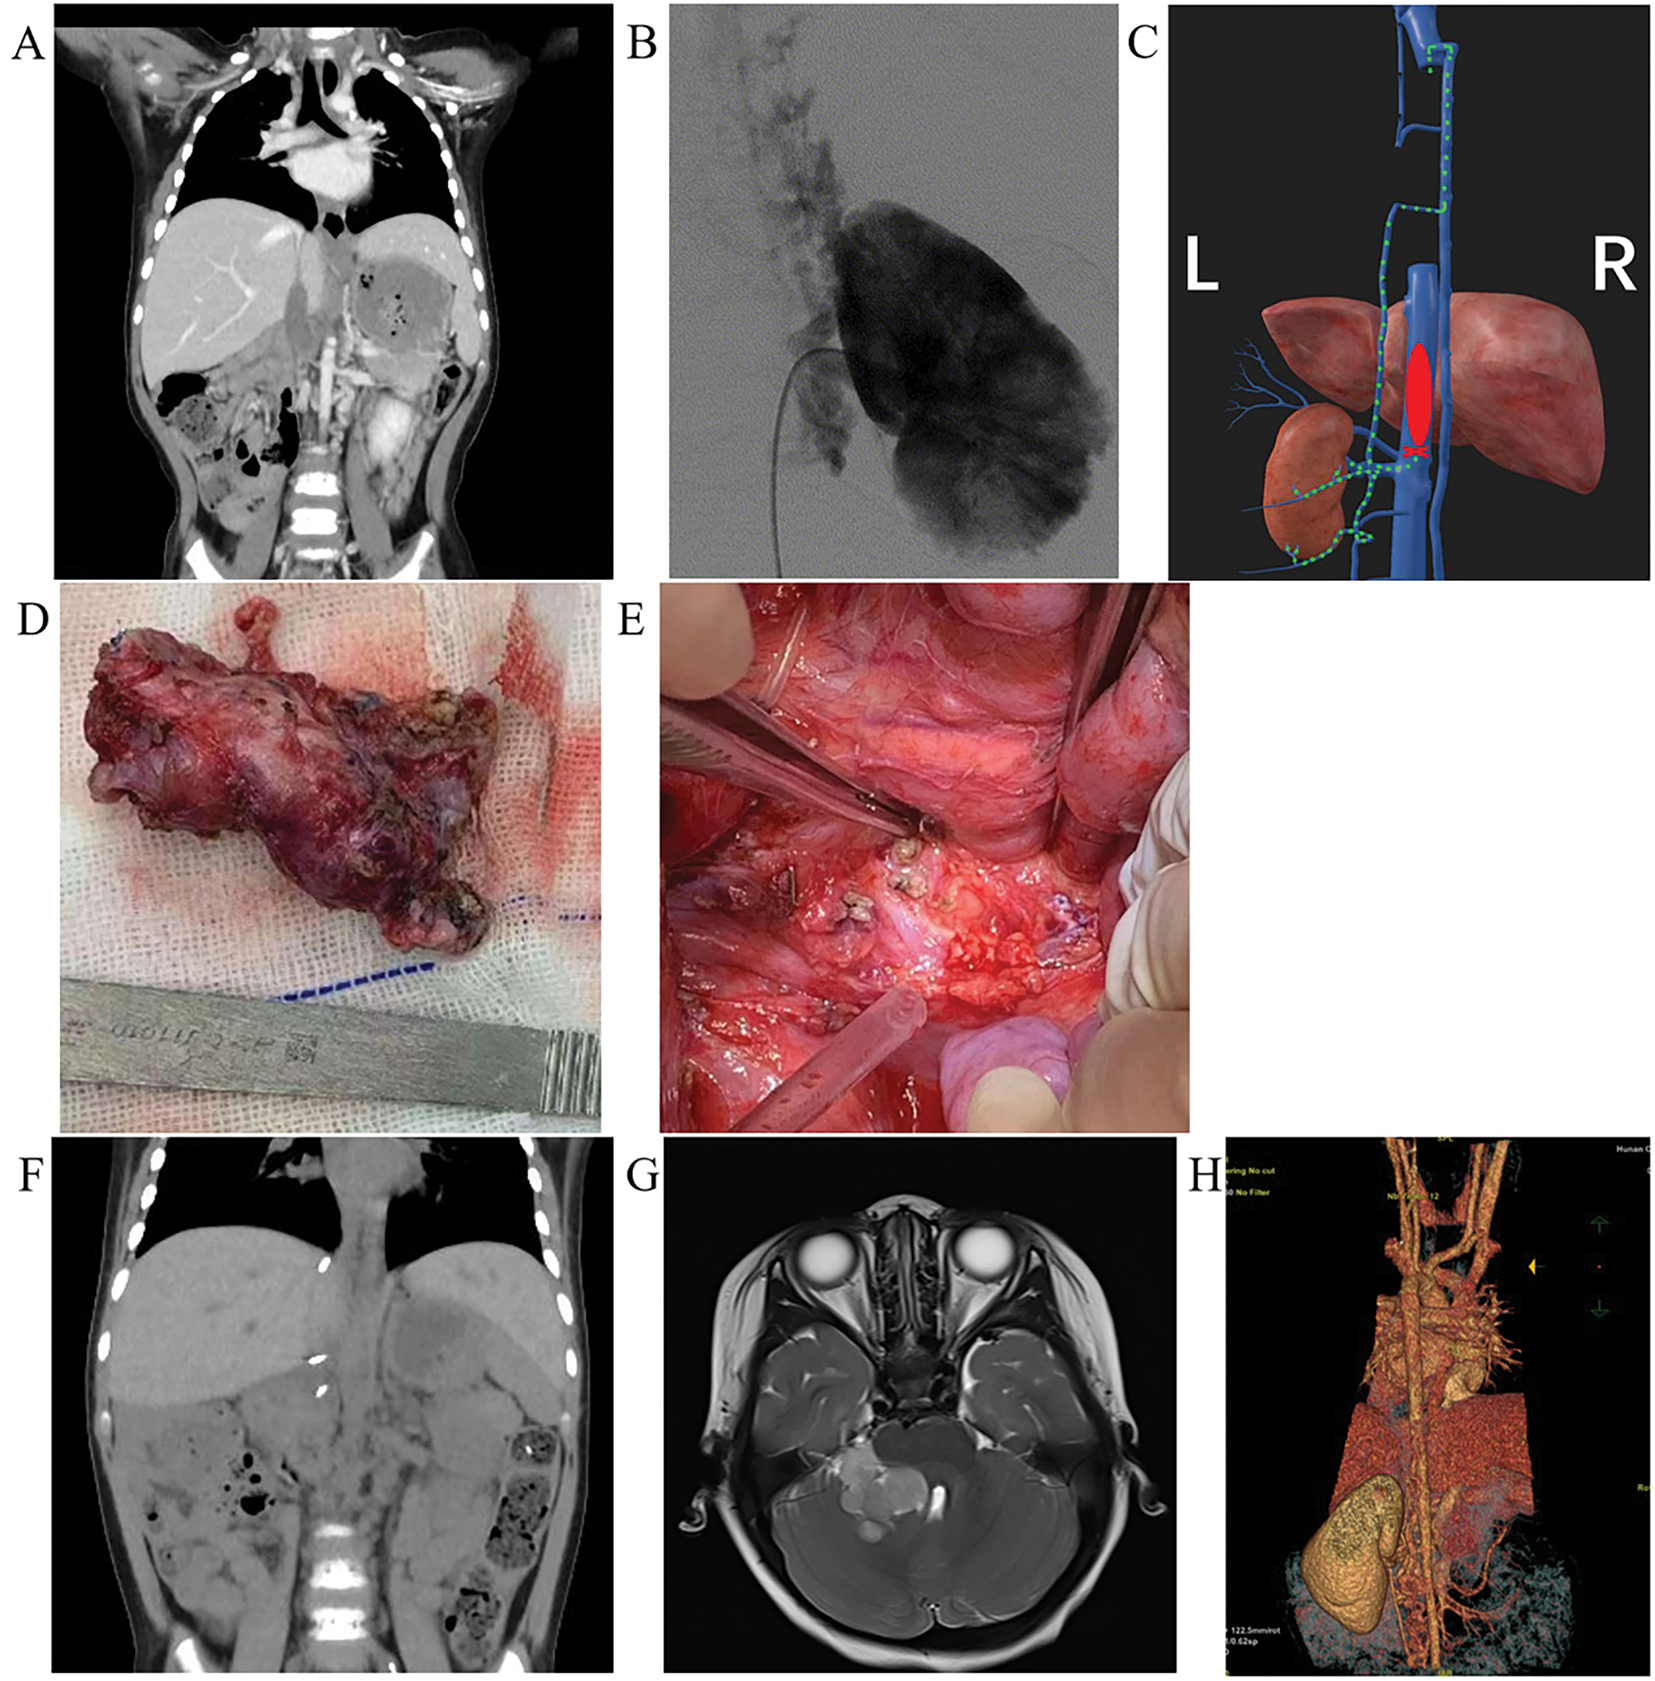

Cross-sectional imaging demonstrated a large right renal mass measuring 12.2 × 9.9 × 8.9 cm with heterogeneous density (8–53 Hounsfield units) and irregular contrast enhancement, causing significant compression of adjacent structures. The IVC below the hepatic segment showed hypodense lesions with heterogeneous enhancement, alongside multiple enlarged retroperitoneal lymph nodes (Figure 2A). IVC ultrasonography revealed a 53 × 16 mm hypoechoic mass extending from the right renal vein-IVC junction to the retrohepatic IVC segment (Figure 2B). Plain chest radiography and contrast-enhanced cranial CT demonstrated interstitial inflammatory changes. Renal function was normal.

FIGURE 2. Radiological and pathological findings in a clear cell sarcoma of the kidney (CCSK) patient treated with right radical nephrectomy and inferior vena cava (IVC) thrombectomy. (A) Abdominal computed tomography (CT) shows a large mass in the right kidney area, with low-density filling in the IVC, compressing surrounding organs. (B) Color Doppler ultrasound shows a hypoechoic mass filling the IVC. (C) Digital subtraction angiography (DSA) shows interrupted contrast flow in the IVC with reflux from the right lumbar vein. (D) Macroscopic specimen of the resected tumor. (E) The thrombus extracted from the opened IVC. (F) Esophageal Doppler ultrasound confirms unobstructed IVC blood flow after thrombus extraction. (G) Microscopic image of tumor cells (H&E staining ×100). (H) BCOR staining of the nuclei of tumor cells (2+). (I) Vimentin staining of the cytoplasm of tumor cells (3+)

In June 2020, an ultrasound-guided percutaneous biopsy of the right renal tumor was performed. Pathology confirmed CCSK with BCOR gene abnormality. Staging revealed Stage III CCSK with Level III IVCTT.9 After diagnosis, the patient received four cycles of chemotherapy (cyclophosphamide, doxorubicin, vincristine, etoposide, and ifosfamide) combined with oral captopril for hypertension management. Post-chemotherapy CT demonstrated extensive tumor necrosis without a significant reduction in tumor or thrombus size.

In November 2020, preoperative digital subtraction angiography (DSA) demonstrated non-visualization of the right iliac vein distal to its junction with the IVC, with extensive collateral circulation bilaterally. The collateral flow coursed through the paravertebral veins to the azygos vein and into the right atrium. A filling defect was observed at the IVC-hepatic vein confluence (Figure 2C).

During surgery, a reverse T incision was made. The procedure involved exploration around the kidney followed by radical resection of the right renal tumor, including right ureterectomy, retroperitoneal lymph node dissection, and IVC thrombectomy. The resected tumor measured approximately 13 × 12.5 × 10 cm, with an intact capsule, dark purple-gray coloration, and soft consistency. An enlarged lymph node (~1 cm) was identified near the right renal hilum and IVC. After mobilizing the liver, the IVC and its major branches were exposed and occluded. The surgical procedure involved incising the IVC, removing the thrombus, repairing the vessel with sutures, releasing vascular clamps, completing perirenal lymph node clearance, and finally closing the abdominal incision (Figure 2D–F). At the junction of the inferior vena cava and right renal vein, the tumor thrombus was found to be tightly adhered to the vessel wall. To avoid damaging the IVC, this portion was carefully excised using sharp dissection.

Histopathological examination with hematoxylin and eosin (H&E) staining demonstrated features consistent with CCSK, including focal cystic degeneration. The tumor infiltrated the renal parenchyma without capsule penetration but showed involvement of the renal pelvis wall. No tumor cells were identified in the renal sinus or hilar vessels. The IVCTT consisted of tumor cells. No tumor cells were identified at the ureter resection margin or in the lymph nodes adjacent to the right renal vein (0/1). Immunohistochemistry results were as follows: Ki-67 (20%), Vim (3+), CyclinD1 (2+), BCOR (2+), CD56 (+), INI-1 (2+) (Figure 2G–I).

During a follow-up visit in March 2022, an abdominal CT scan revealed narrowing in narrowing in the hepatic segment of the IVC, along with partial contrast filling defects in the lower and infra-hepatic IVC segments. Additionally, numerous vascular shadows were observed distally (Figure 3A), consistent with IVCTT recurrence. Subsequent DSA findings confirmed IVC obstruction at the L1/2 level, with contrast medium draining into the bilateral vertebral venous plexus and ultimately into the superior vena cava. Notably, the distal left renal vein did not empty into the IVC but instead communicated with the hemiazygos vein via the perirenal venous plexus (Figure 3B,C).

FIGURE 3. Imaging and intraoperative findings in a patient undergoing partial inferior vena cava (IVC) resection and thrombectomy. (A) Computed tomography (CT) imaging in March 2022 shows inferior vena cava tumor thrombus (IVCTT) recurrence at the hepatic segment and the infrahepatic segment of the IVC. (B) Intraoperative digital subtraction angiography (DSA) reveals contrast agent draining from the left renal vein into the hemiazygos vein. (C) Schematic diagram shows retrograde left renal blood flow (green dashed arrow) secondary to IVC occlusion by the thrombus (red ellipse). (D) The intraoperative findings show the resected thrombus and partial IVC. (E) The exposed part of the retroperitoneum after the resection of the thrombus and partial IVC. (F) Postoperative reassessment at three months based on CT shows complete resection of the thrombus with no recurrence. (G) Postoperative cranial magnetic resonance imaging (MRI) at 15 months shows a mass in the right cerebellopontine angle area, measuring approximately 3.4 × 3.2 × 3.7 cm, with slightly prolonged T1 and T2 signals, and significant enhancement observed after contrast. (H) Postoperative single-energy vascular imaging (posterior view) at 15 months shows occlusion of the left renal vein and tortuous dilatation of the hemiazygos vein and left spermatic vein

The surgical procedure involved partial resection of the inferior vena cava, tumor thrombectomy of the inferior vena cava, and partial resection of the left renal vein through the same incision site used in previous operations. The left renal vein was dissected and suspended. Working from inferior to superior, the inferior vena cava was dissected and encircled with a horizontal sling placed 2 cm below the left renal vein. The scar tissue surrounding the liver was released, and the second hepatic portal was mobilized. The anterior, left, right and posterior walls of the IVC were fully dissociated, and a blocking band was placed around the IVC below the diaphragm. Intraoperative ultrasound confirmed the thrombus was contained within the occluded segments of each vessel. Sequential vascular occlusion was performed in the following order: the subphrenic IVC, followed by a segment 2 cm below the left renal vein, and then 1.5 cm distal to the left renal vein. After occluding the thrombus-containing IVC segment proximally and distally, there was no evidence of abdominal organ congestion, with maintained cardiac output, normal urine production, and absence of lower limb edema, indicating adequate IVC collateral circulation. The inferior vena cava and its branches were transected between the second hepatic portal to the left renal vein. A 3 cm segment of inferior vena cava containing the tumor thrombus were resected (Figure 3D,E), with the proximal stump closed using 5-0 PROLENE sutures. The subdiaphragmatic IVC occlusion was then released after 10 min of hepatic vascular isolation. After all the blood vessels were sutured, the remaining vascular flows were blocked for approximately 30 min. The abdomen was then closed, completing the surgical procedure. Pathological examination demonstrated tumor cells within the IVC lumen and adjacent vascular wall, without extension into surrounding tissues or metastasis involvement of regional lymph nodes.

Following the surgical procedure, the patient received five cycles of chemotherapy (ifosfamide, etoposide, vincristine, and irinotecan) and underwent regular follow-up at Hunan Children’s Hospital. A postoperative abdominal CT scan performed three months after surgery showed no tumor recurrence or residual thrombus (Figure 3F). During a subsequent outpatient review in June, the patient was in good general condition, with no evidence of superficial lymph node enlargement, abdominal pain, lower limb edema, varicose veins, or other symptoms. Renal function tests were normal. Unfortunately, the patient returned to our hospital 15 months after surgery due to persistent head tilt and along with right eye deviation lasting for more than 10 days. While an abdominal CT scan showed no recurrent lesions, a head magnetic resonance imaging (MRI) revealed a space-occupying lesion in the right cerebellopontine angle, suggesting a malignant brain tumor (Figure 3G). Despite recommendations for further treatment, the patient’s parents declined. The patient subsequently died.